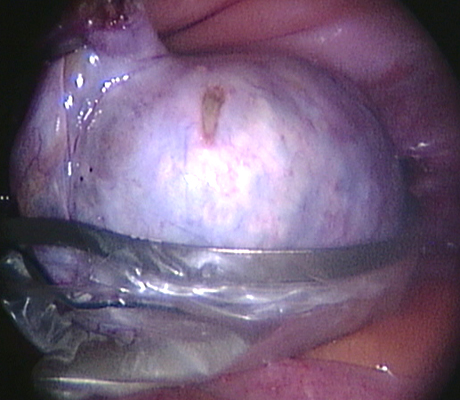

Examples of some pelvic masses dealt with by key-hole surgery.